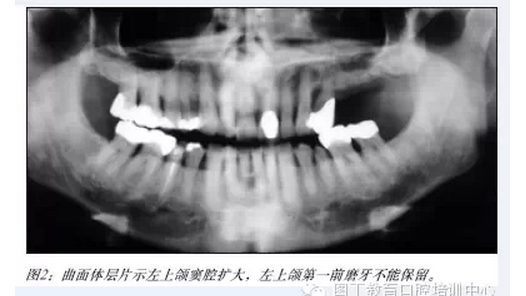

【口腔種植】上頜竇提升植骨術(shù):一項(xiàng)矢狀層植骨技術(shù)